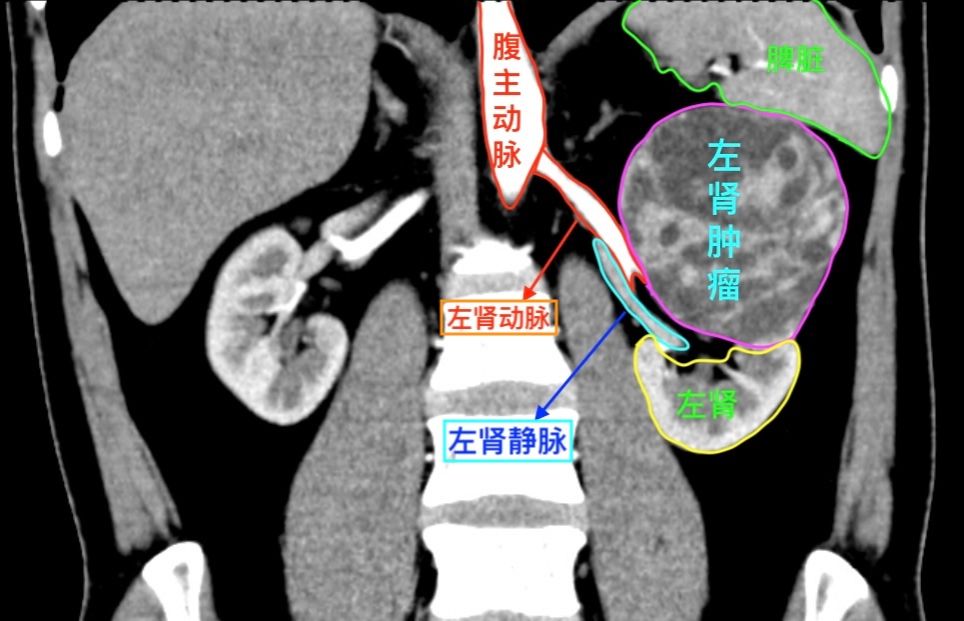

患者文先生在一次常规体检中,意外发现左肾存在一个巨大占位。进一步的增强CT检查结果令人倒吸一口凉气:一个大小约93×82×90mm的类圆形肿瘤从肾脏突出,位置极其凶险,紧贴着肾门部的大血管和集合系统。经专业评估,该肿瘤R.E.N.A.L评分高达11分,属于“高度复杂”级别。

(冠状位影像更完整地展现了肿瘤与肾脏的毗邻关系)